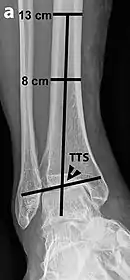

Tibiotalar surface angle (TTS)

Varus or valgus deformity, if suspected, can be measured with the frontal tibiotalar surface angle (TTS), formed by the mid-longitudinal tibial axis (such as through a line bisecting the tibia at 8 and 13 cm above the tibial plafond) and the talar surface.[23] An angle of less than 84 degrees is regarded as talipes varus, and an angle of more than 94 degrees is regarded as talipes valgus.[24]